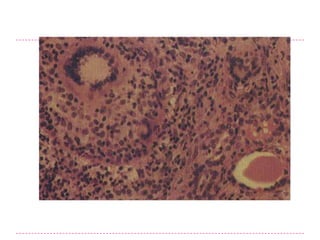

Morfologia  Puede identificarse2 fase: -Fase Hiperplasica -Fase de involucion coloidea La glandula tiroides esta difusa y Si la dieta de yodo aumenta simetricamente aumentada, aunque el posteriormente , o si la demanda de incremento es usualmente moderado y la hormonas tiroideas desciende, el epitelio glandula raramente excede de 100 a 150g. folicular estimulado involuciona hasta formar una glandula aumentada, rica en Los foliculos estan delimitados por celulas coloide (bocio coloide). columnares que pueden apilarse y formar proyecciones. En estos casos, la superficie de corte de la glandula tiroides es usualmente El acumulo no es uniforme a traves de la marron, algo cristalina y translucida. glandula, y algunos foliculos estan enormemente distendidos, mientras que HISTOLOGICAMENTE: el epitelio folicular otros permanecen pequenos. es aplanado y cuboidal, y el coloide es abundante durante los periodos de involucion.

morfologia • Multilobulados, asimetricos y producen aumentos de tamano de las glandulas que pueden lograr un peso de mas de 2000g • El patron de aumento es bastante impredecible y puede afectar a un lobulo mas que a otro, provocando una presion lateral, sobre la traquea y el esofago. • En otros casos el bocio crece detras del esternon y las claviculas produciendo lo que se denomina bocio intratoracico o sumergido. • Ocasionalmente, la mayoria del mismo se encuentra oculto detras de la traquea y el esofago; en otros casos solo sobresale un nodulo, dando la apariencia de un nodulo solitario. • Al corte se observan nodulos irregulares que contienen cantidades variables de coloides marron y gelatinoso. Son frecuentes los cambios regresivos, particularmente en las lesiones mas antiguas, e incluyen areas de hemorregia, fibrosis, calcificacion y cambios quisticos. • La apariencia microscopica revela foliculos ricos en coloides delimitados por epitelio inactivo adelgazado y areas de hipertrofia epitelial folicular e hiperplasia